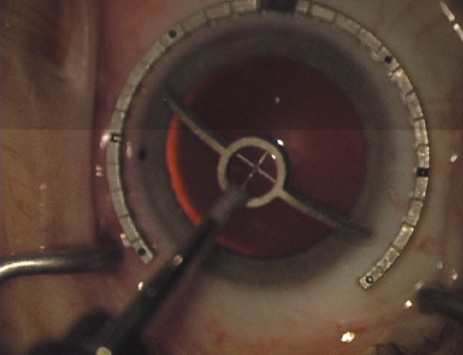

Proper centration of the incisions over the steep corneal meridian is of utmost importance. Increasing evidence supports the notion that significant cyclotorsion may occur when assuming a supine position.32 As previously noted, an axis deviation of only 15 degrees may result in a 50% reduction of surgical effect.5 For this reason, most surgeons advocate placing an orientation mark at the 12:00 or 6:00 limbus while the patient is in an upright position. This is particularly important when employing injection anesthesia wherein unpredictable ocular rotation may occur. An additional measure that may be employed to help center the relaxing incisions is to identify the steep meridian (plus cylinder axis) intraoperatively using some form of keratoscopy. The steep meridian over which the incisions are to be placed corresponds to the shorter axis of the reflected corneal mire. A simple handheld device such as the Maloney (Storz, Katena) or Nichamin (Mastel Precision) keratoscope works well, or a more robust and well-defined mire may be obtained through an elaborate microscope-mounted instrument such as the Mastel Ring of Light (Mastel Precision). Another common way in which the steep meridian is marked utilizes a Mendez Ring or similar degree gauge that is aligned with the previously placed limbal orientation mark, and the cylinder axis is then located on the 360-degree gauge.

The extent of arc to be incised may be demarcated in several different ways. Our preferred method makes use of a modified Fine-Thornton fixation ring (Nichamin Fixation Ring and Gauge; Mastel Precision, Storz, Rhein Medical). This instrument serves to fixate and position the globe in order to optimize incision placement, as well as to delineate the extent of arc to be incised. One visually extrapolates from the limbus to marks on the surface of the ring. Each incremental mark is 10 degrees apart, and bold hash marks (180 degrees) opposite to each other serve to align and center the incision over the steep meridian. This approach obviates the need to ink and physically mark the cornea. If one desires, particularly when first gaining experience with LRIs, a two-cut RK marker may be used to place ink marks upon the cornea to show the exact extent of arc that is to be incised, in conjunction with the fixation ring/gauge (Fig. 4). Alternatively, various press-on markers are available, such as those made by Rhein Medical (Dell-Nichamin Marker, Nichamin-Kershner Marker, or the Ruminson Marker) (Fig. 5). ASICO and other instrument companies offer a full line of dedicated markers, rings, and blades for performing LRIs.

Fig. 8. Steep meridian is confirmed intraoperatively by keratoscopy. In this left eye viewed from the temporal side, the “short axis” of the corneal mire is seen to be at the 75-degree meridian. (Reprinted from Hardten DR, Lindstrom RL, Davis EA. Phakic Intraocular Lenses: Principles and Practice. Thorofare, NJ: SLACK Incorporated, 2004, with permission.)

Fig. 20. Keratoscopy, after lifting of the speculum to relieve induced pressure and distortion of the corneal mires, confirms the steep axis of 85 degrees.